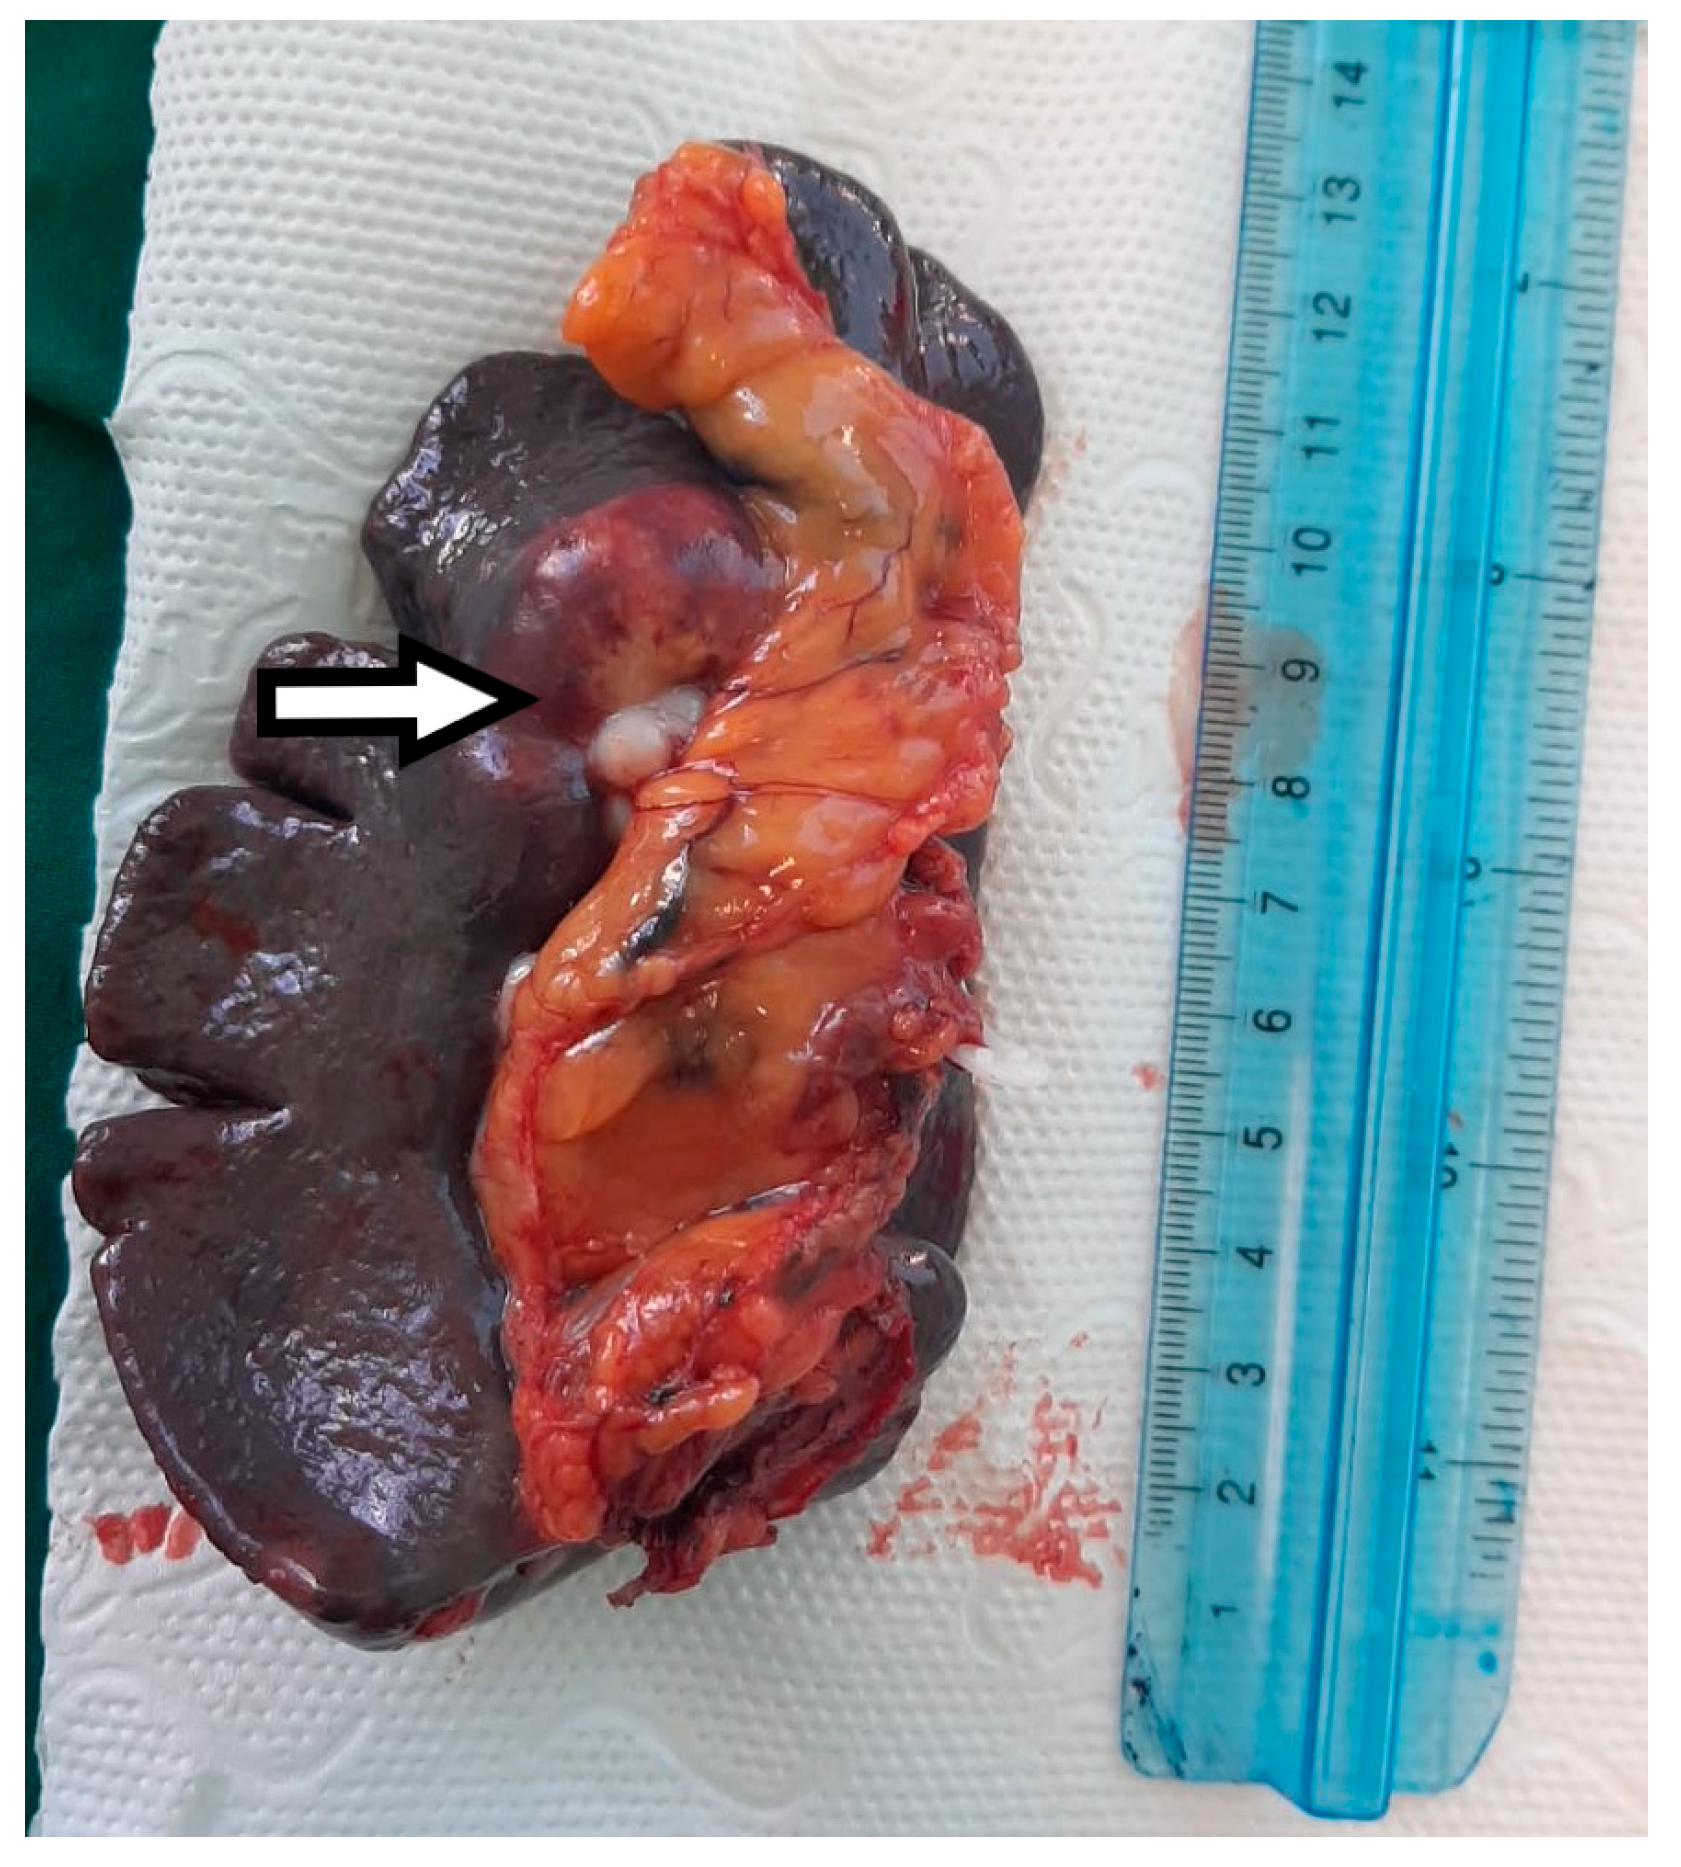

Figure 5.

The macroscopic appearance of the splenectomy specimen with a hilar metastatic gastric cancer tumor indicated by the white arrow.

Macroscopic histopathological examination of the resection specimen revealed a spleen measuring 15/10/4 cm with whitish solid tumors located at the hilum and subcapsular (Figure 5). Microscopically, splenic parenchyma with distorted architecture was identified due to areas of intestinal-type adenocarcinoma (Figure 6). No tumor invasion was observed in the station 10 lymph nodes.